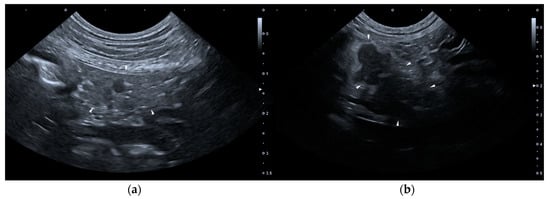

None of the dogs met the required criteria for group B. As for group C (constituted by 14 dogs), on T0 none of the dogs presented HSAs, but two dogs presented two or more PSAs: one of them presented wall thickening and corrugated appearance of duodenum and paralytic ileus, the other one showed wall thickening of the stomach, paralytic ileus and dilation of the common bile duct. Six dogs belonging to group C presented one or more PSAs on T1. Figure 2 shows two ultrasound images of the pancreas of a dog included in the Group C, of T0 and T1, respectively.

Figure 2. Ultrasound images of the right lobe of the pancreas of a dog included in the group C. (a) T0: transverse sonogram of the pancreas, which is normal in size, shape, echogenicity, and echostructure; (b) T1: longitudinal sonogram of the pancreas, which is slightly enlarged and inhomogeneous, hypoechoic and with peripancreatic hyperechoic mesenteric fat. T0: abdominal ultrasound examination performed on the first day of hospitalization; T1: abdominal ultrasound examination performed on the third day of hospitalization.

The dogs belonging to group C showed a clinical presentation consistent with AP and an abnormal result at the SNAP cPL test; however, they had an AUE positive for AP only on T1. We hypothesize that these dogs had not yet developed such extensive damage on T0, which instead manifested itself on T1. This was assumed from the pathophysiology of AP which shows initial acinar cell damage that could subsequently affect the entire organ and also the peritoneal cavity [4]. We hypothesize that at hospital admission, there was microscopic cellular damage in these dogs, which resulted in a release of cPL in the blood circulation which in turn led to the abnormal SNAP cPL test result. In these 14 dogs, the AUE became positive between the first and the second checks as hypothesized by Hecht and Henry, and similarly to humans, where only in 20% of cases the pancreas demonstrates signs of AP on AUE before 48–72 h after symptom onset [15,23].